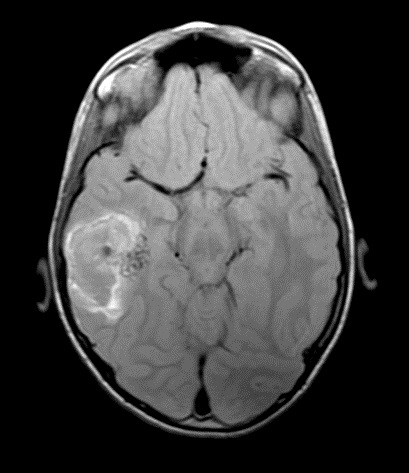

Diagnóstico de Malformação Arteriovenosa Cerebral após Traumatismo Craniano

Images in Pediatrics